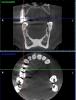

Slavik111 Опубликовано 5 июля, 2010 Автор Поделиться Опубликовано 5 июля, 2010 (изменено) Спасибо за ответ.Вот панорама.Вывод о том, что после удаления 16 и 17 образуется соустье, хирург сделал после просмотра 3Д снимка - это большая программа, ее сюда не закачать. Изменено 5 июля, 2010 пользователем Slavik111 Ссылка на комментарий

Slavik111 Опубликовано 5 июля, 2010 Автор Поделиться Опубликовано 5 июля, 2010 (изменено) Мне к сожалению снимки оттуда не выдернуть - это программа на диске которая сама демонстрирует свои снимки. Кажется формат DICOM. Но я попробую выдернуть (через копию экрана) пару продольных снимков этих зубов.Мне хирург сказал, что есть соустье или нет выяснится непосредственно после удаления. То естькак повезет. И если не повезет\, надо будет вскрывать пазуху и чистить гной перед ушиванием.Отличается ли эта операция по чистке от ЛОР операции на пазухе? (менее травмотична?)Можно ли при наличии какого-то минимального кол-ва гноя вообще не чистить пазуху у стоматолога, а просто - удалить, если соустья - зашить и пойти к ЛОРу промывать пункцией? Изменено 5 июля, 2010 пользователем Slavik111 Ссылка на комментарий

Slavik111 Опубликовано 5 июля, 2010 Автор Поделиться Опубликовано 5 июля, 2010 (изменено) Названия файлов - номера зубов. Еще 17-й зубhttp://saveimg.ru/show-image.php?id=b293d8...a9dc1c7d74bba31http://saveimg.ru/show-image.php?id=8c6420...92ba92c9a149318http://saveimg.ru/show-image.php?id=0660de...848084cfe5e2b22 Изменено 5 июля, 2010 пользователем Slavik111 Ссылка на комментарий

Slavik111 Опубликовано 6 июля, 2010 Автор Поделиться Опубликовано 6 июля, 2010 Согласен. + Все может оказаться еще проще, удалят, сообщения не будет, гайморит пройдет быстро. Насчет сообщения - я специально 4 снимка 17-го зуба приложил - там с моей точки зрения корни прямо в пазуху торчат (если это однородное пространство над корнем - пазуха).Или я не прав и это не пазуха? Большое спасибо за советы! Только что был на приеме у ЛОРа. 9-я пункция - вытянула немного (может 5 мл) шприцом желтого полупрозрачного секрета - сказала что киста. Затем промывала долго - 2 банки вылила - гной только вначале, примерно 1 чайная ложка (может меньше). По сравнению с позапрошлым разом - гораздо меньше.Извините, уважаемые, но несмотря на Ваши советы подписал отказ от госпитализации.След. пункция в четверг. ЛОР сердилась за мой отказ,сказала что меньше гноя уже не будет, но затем смягчилась (потому что ничего больше у меня не болит и насморка нет) и сказала что решим по результатам пункции в четверг.На самом деле я буду думать - я понимаю что в стационаре лучше, но раз все-таки меня соблазнили "более легким" путем - если без гноя то амбулаторно - то получается есть из чего выбирать. В черьверг, чувствую, уже не будет из чего выбирать Ссылка на комментарий